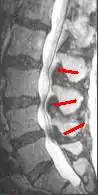

Helpful imaging may include x-rays, CT, CT myelogram, and magnetic resonance imaging (MRI), but MRI is preferred.[1] Abnormal MRI findings may be present in two-thirds of asymptomatic individuals, and imaging findings of spinal stenosis do not correlate well with symptom severity. Therefore, imaging findings must be considered in the context of a patient's history and physical exam when seeking a diagnosis.[2] The evidence for using objective imaging findings to define NC has been conflicting.[12]